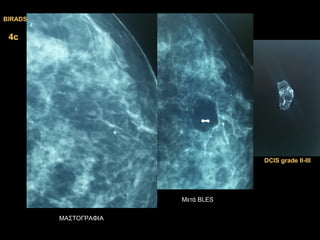

4b4b

2.DCIS grade II2.DCIS grade II

1.DCIS grade III1.DCIS grade III

Μετά BLES

ΜΑΣΤΟΓΡΑΦΙΑ

BIRADSBIRADS

4c4c

DCIS gradeDCIS grade ΙΙ-ΙΙ-IIIIII